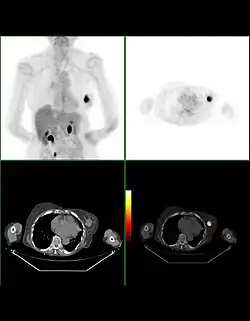

Beim PET/CT wird der Patient unmittelbar hintereinander durch beide Detektorringe (Gantries) von CT und PET gefahren. Da der CT-Datensatz für die Rekonstruktion der PET-Daten benötigt wird, wird in der Regel zunächst eine CT-Aufnahme durchgeführt und die PET-Aufnahme daran angeschlossen. So kann bereits nach Beendigung der Aufnahme der ersten Bettposition mit der Bildrekonstruktion begonnen werden. Würde zunächst der PET-Datensatz aufgenommen, müsste mit dem Beginn der Bildrekonstruktion der PET-Daten gewartet werden, bis der CT-Datensatz rekonstruiert ist und zu unerwünschten Verzögerungen im Arbeitsablauf führen, denn die Rekonstruktion eines Ganzkörper-PET-Datensatzes benötigt je nach Gerät und Rechenmethode ca. 10–45 Minuten Zeit. Eine laufende CT-Aufnahme ist für den Patienten daran erkennbar, dass der Tisch bewegt wird, während gleichzeitig ein Motorengeräusch hörbar ist, das in erster Linie von der Rotationsbewegung von Röhre und Detektorsystem stammt. Die Gantries sind bei einigen Systemen im selben Gehäuse untergebracht und nicht einzeln von außen sichtbar. Die errechneten Bilder werden im Computer automatisch fusioniert.

Befundung

Die Befundung des PET- oder PET/CT-Bildes erfolgt durch Betrachtung der rekonstruierten Schnittbilder (axial, koronar oder sagittal). Bei PET/CT-Geräten ist die Darstellung von PET und CT verknüpft, so dass automatisch die Position des korrelierenden PET-Bildes gezeigt wird, wenn der Bildkursor im CT-Bild verschoben wird.

Für eine Übersichtsdarstellung wird ein sogenanntes MIP-Bild (Maximum Intensity Projection) herangezogen. In dieser Darstellung ist das gesamte Untersuchungsobjekt abgebildet und man erlangt einen schnellen Überblick über Regionen erhöhter Aufnahme. Zur nochmals besseren Visualisierung kann man das MIP um sich selbst rotieren lassen, um das Untersuchungsobjekt von allen Seiten zu zeigen.